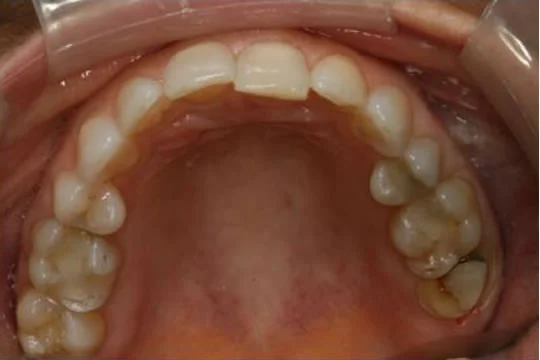

Dr. Halabo’s work reversed 40 years of deterioration and the result made my smile look 40 years younger.

As far as I am concerned, Dr. Halabo has saved my teeth. The fact that they look nice also is just icing on the cake! I hope that Dr. Halabo will be my dentist for life.

Thanks Dr. Halabo for giving me the ability to eat steak again and the great smile too-my wife loves it.